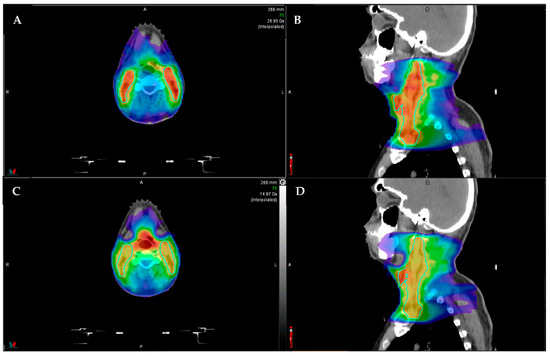

- McDonald, B.A.; Vedam, S.; Yang, J.; Wang, J.; Castillo, P.; Lee, B.; Sobremonte, A.; Ahmed, S.; Ding, Y.; Mohamed, A.S.; et al. Initial Feasibility and Clinical Implementation of Daily MR-Guided Adaptive Head and Neck Cancer Radiation Therapy on a 1.5 T MR-Linac System: Prospective R-IDEAL 2a/2b Systematic Clinical Evaluation of Technical Innovation. Int. J. Radiat. Oncol. 2020, 109, 1606–1618. [Google Scholar] [CrossRef] [PubMed]

- Bahig, H.; Yuan, Y.; Mohamed, A.; Brock, K.K.; Ng, S.P.; Wang, J.; Ding, Y.; Hutcheson, K.; McCulloch, M.; Balter, P.A.; et al. Magnetic Resonance-based Response Assessment and Dose Adaptation in Human Papilloma Virus Positive Tumors of the Oropharynx treated with Radiotherapy (MR-ADAPTOR): An R-IDEAL stage 2a-2b/Bayesian phase II trial. Clin. Transl. Radiat. Oncol. 2018, 13, 19–23. [Google Scholar] [CrossRef] [Green Version]